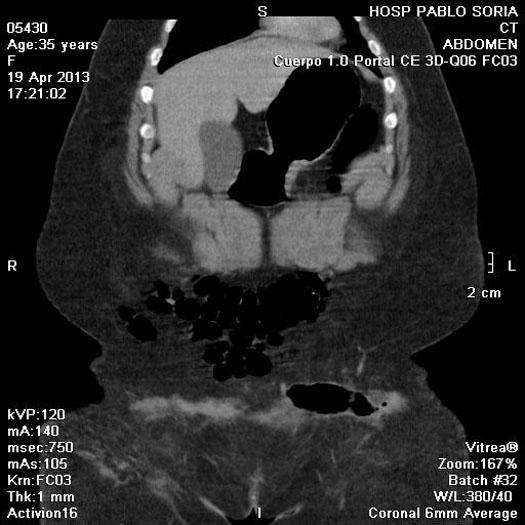

TAC

Paciente femenina, 45 años de edad, IMC > 35, (>) ingresa tras sufrir un accidente automovilístico por volcamiento. Sentada en el asiento de atrás con cinturón de seguridad a dos dedos en la cintura. Luego de 14hs del accidente ingresa al servicio de emergencia, lúcida, Glasgow 15, con dolor intenso en miembro inferior izquierdo y tatuaje de cinturón de seguridad a nivel de pelvis. Se realiza TAC de emergencia y se somete a una laparoscopia diagnóstica por descenso del Hto en 5 puntos. Se reconvierte a una laparotomía media , se sutura el mesosigma desgarrado y una laceración del sigma. Se constata hernia traumática con sección completa de pared anterolateral del abdomen. Se deja Abdomen abierto y contenido.